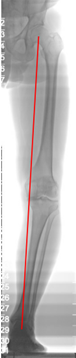

• Kompletterar utredning med: HKA-röntgen Hip- Knee- Ancle

o Mekanisk axel ”ska vara” 0 grader

o Medial artros ger varusfelställning av benet (vilket Ulf har!) 9/10 som har artros har medial artros. Glappigt på laterala sidan

Patienten opererades med en total knäprotes

• Mekaniska axeln vid lyckad op återställd till?

A

0 grader